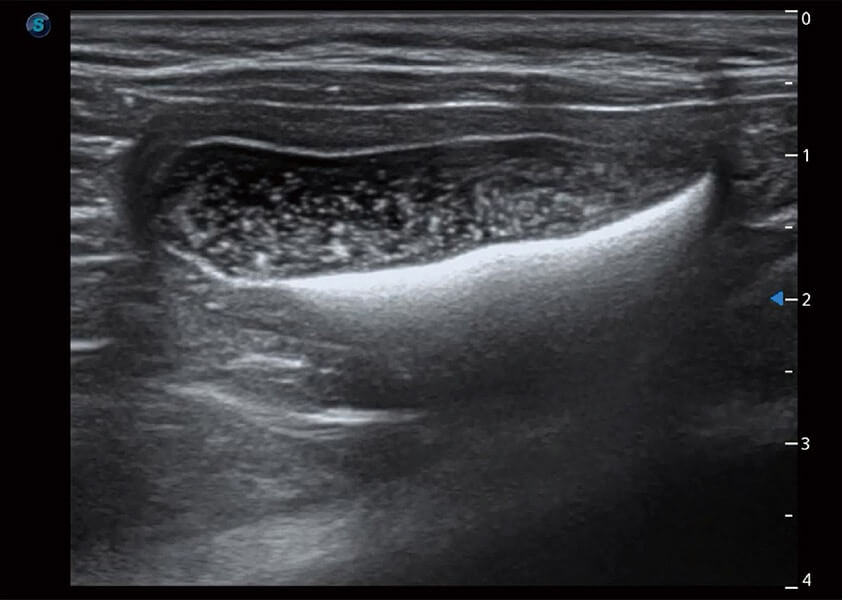

ProPet 60 作為一款高端臺式動物超聲設(shè)備,為動物醫(yī)生的日常診斷提供了一系列貼合動物臨床需求、解決臨床實(shí)際問題的高級成像功能。憑借全系列高清探頭,滿足醫(yī)生對腹部、心臟、生殖、淺表、肌骨等成像的所有需求,切實(shí)幫助您提升檢查效率,提高診斷信心。